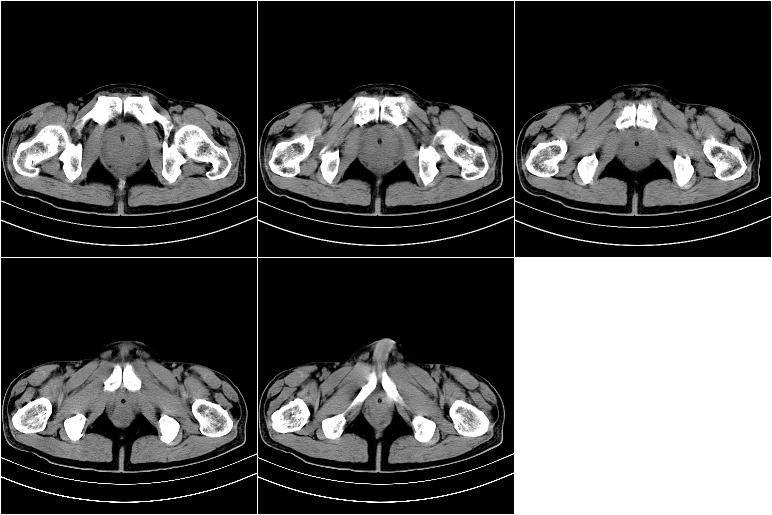

标题: CT21568:男,57岁,双肾及输尿管重度积水。彩超示前列腺占 [打印本页]

标题: CT21568:男,57岁,双肾及输尿管重度积水。彩超示前列腺占

考虑前列腺增生并慢性尿潴留致膀胱肌小梁增生

考虑前列腺增生并慢性膀胱炎。不除外前列腺癌可能。建议结合其它检查。

考虑:前列腺增生并慢性膀胱炎。不除外前列腺癌可能。建议结合其它检查。